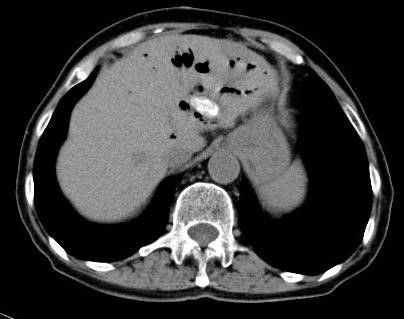

ct平扫显示胆总管内结石,支直径约12mm